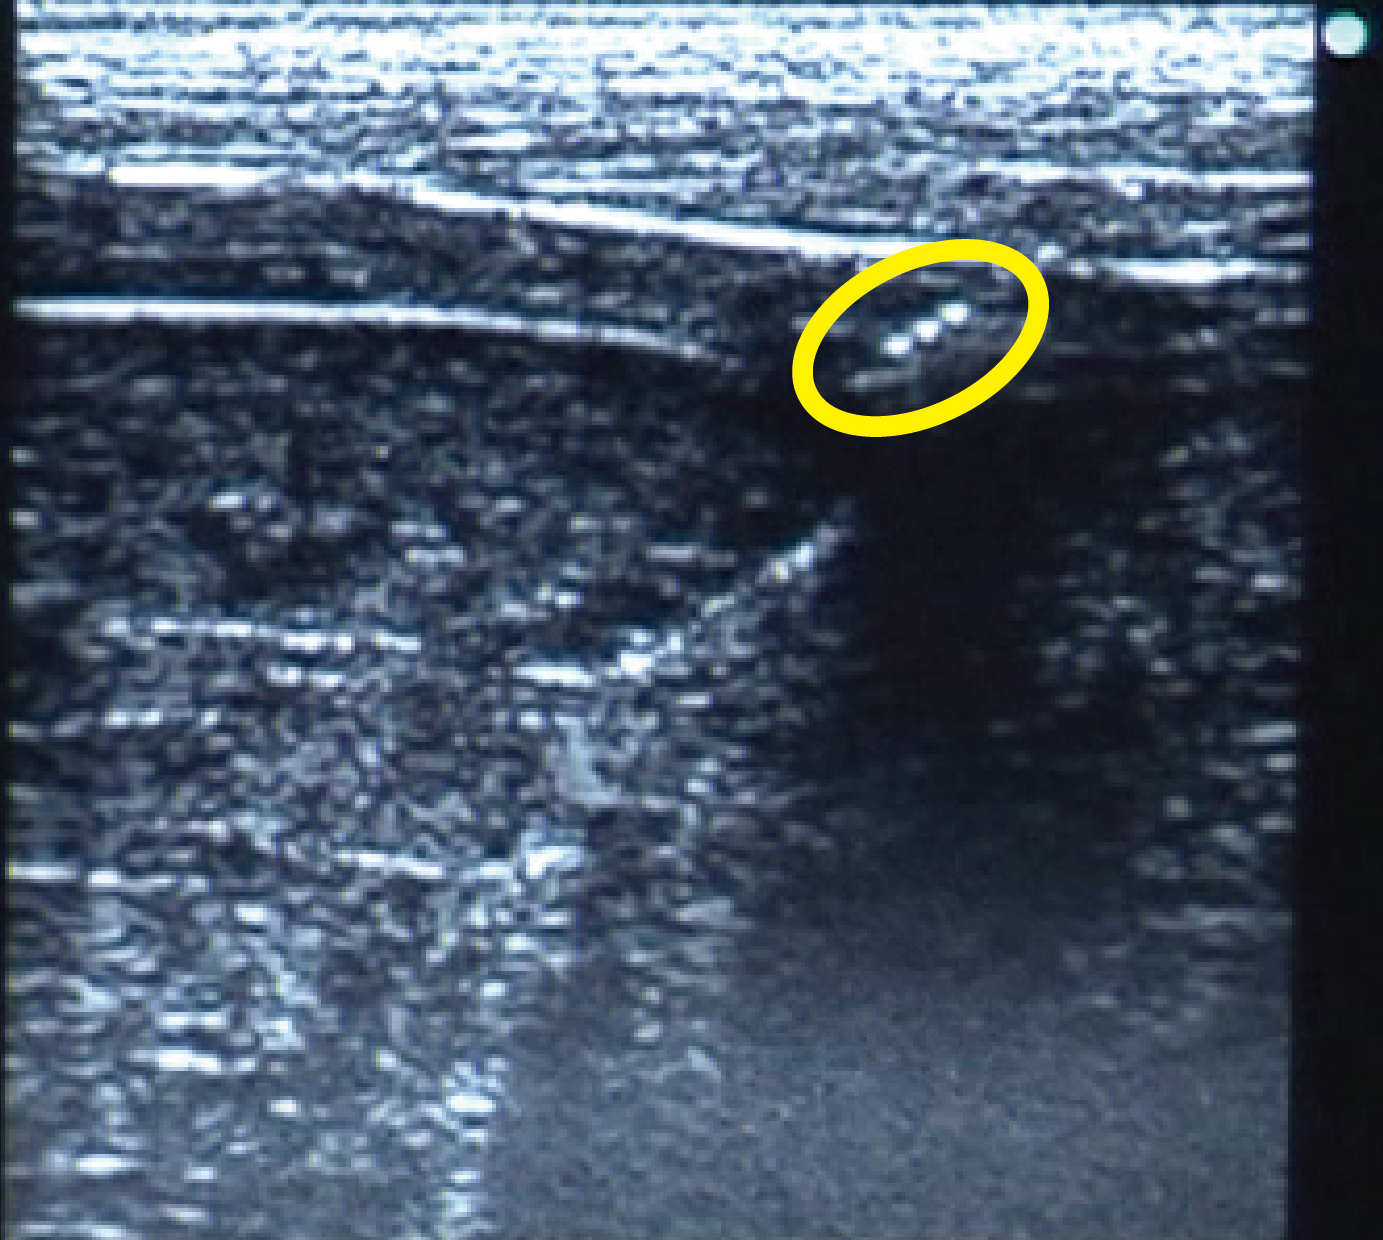

本発明は、超音波映像を観察しながら体内の目的部位へ針管を穿刺する超音波対応穿刺針に関するもので、穿刺針の所定位置に三角錐のコーナーキューブミラーを設けることで超音波下での針管の視認性を向上させたものである。

従来の超音波対応穿刺針は、体表に対して穿刺角度が大きくなる等の条件により、針管の超音波映像が極端に不明瞭になるという問題があった。これに対し、超音波の入射角と出射角が常に平行となる再帰反射に着目し、この性質をもつコーナーキューブミラーを針管の中心軸に平行に複数列、また、長手方向に複数列の配置で加工することにより、穿刺条件等によらず、針管の超音波映像を明瞭なものとした。

本発明を疼痛緩和のため神経近傍に穿刺する神経ブロック針に適用すると、明瞭な超音波映像により、穿刺の際、神経損傷や血管穿刺などの懸念が低減された安全な施術ができる。また、針管を適正位置に穿刺できるため、確実な除痛効果が期待される。